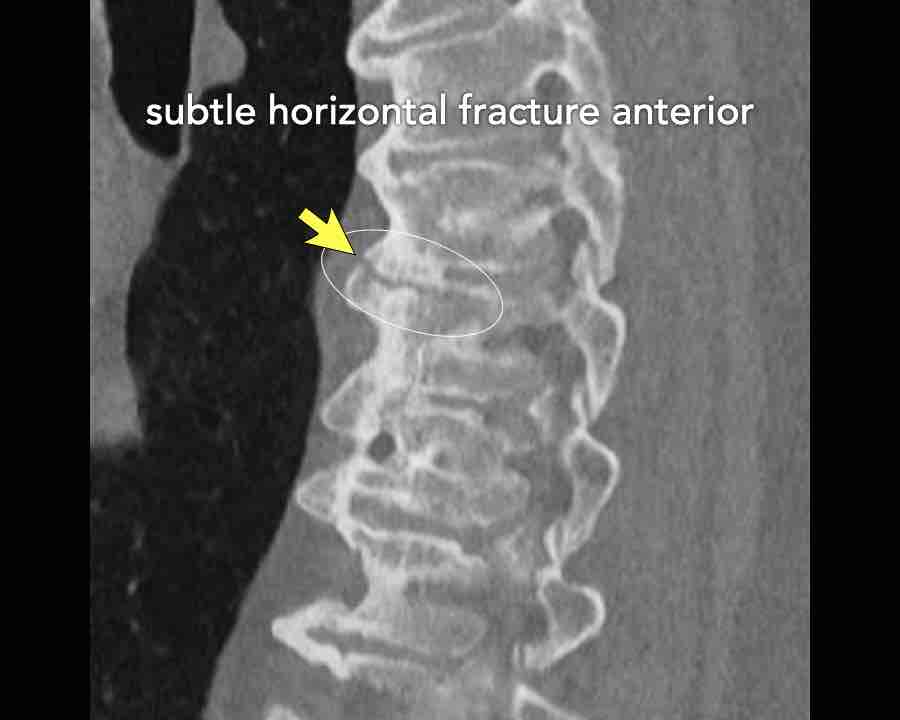

Scroll through images.

What are the findings?

Findings

- C injury? No.

- Signs of a rigid spine?

Yes, clear example of SpA so be aware of a B3 injury. - Horizontal fracture of vertebral body (white circle)

- Subtle separation anteriorly at the fracture level

Conclusion

injury type B3.